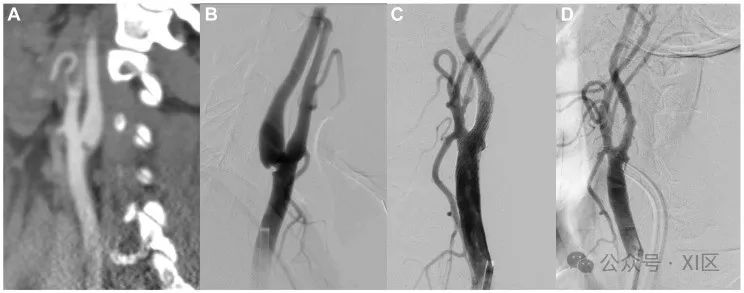

图5支架置入前后CT和DSA显示的颈动脉蹼示例。(A) CT扫描冠状切面上靠近分叉处的右颈内动脉蹼。(B) DSA前后切面显示分叉处的颈动脉蹼充盈缺损和湍流。(C和D)前正位(C)和侧位(D)切面上支架置入后的右颈动脉。未来方向